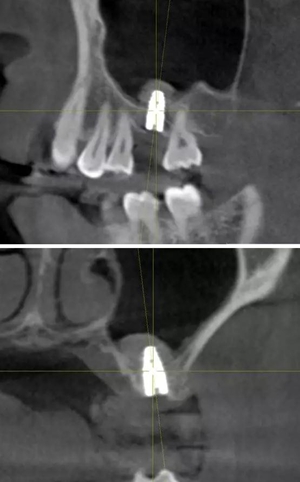

術(shù)后CBCT

提升時(shí)相關(guān)步驟可參考下面圖片

可見(jiàn)在完善的檢查和適當(dāng)?shù)墓ぞ哌x擇下可順利完成較復(fù)雜的上頜竇手術(shù)。